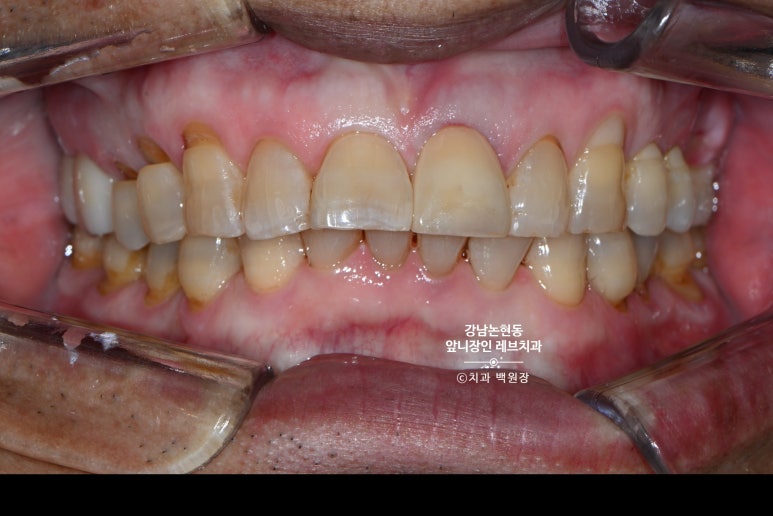

최대한 인접한 치아의 색상과 형태를 반영하여 제작된 지르코니아 크라운 입니다.

정확히는 포세린으로 빌드업한 지르코니아 크라운이죠?

치아의 모양도 모양이지만, 약간 회색빛이 도는 색감과 세월의 흔적이 느껴지는 짙은 베이지색의 느낌.. 그리고 약간의 줄무늬까지 반영해서 제작하였다고 합니다.

디지털 카메라 앞에서 굴욕없는 피부가 거의 없듯, 사실 이렇게 사진상에서 이만큼 적합한 모양과 형태 그리고 색상을 갖게 하는 것이 너무너무 어려운 일입니다.

이 정도면 환자분 입안에 있는 그 자연스러움은 상상을 초월하죠.!!!!!!!!!!!!

Before & After

마지막은 왼쪽 위 가운데 앞니의 치료 전과 치료 후 사진으로 마무리 해보겠습니다.

그래서 이렇게 홀수.. 특히 1개의 보철물을 치료하는 케이스가 제일 어렵습니다.

크라운 하나 빼고는 모두 자연치인 환경에서, 적절히 자연스럽게 하는건.. 예술작품을 하나 만들어내는 것과 같죠.

특히나 이번 환자분의 경우엔, 60대 나이를 가진 분으로

치아 고유의 마모도 심했고, 색상도 독특하며 옅은 가로줄무늬까지 있었습니다.

어렵게 하는 조건이 겹치면서 난이도 급상승 !!!

오히려 그냥 하얗게, 예쁘게 만드는 것을 더 쉬운 치료로 만들어버리는 그런 치료였습니다-